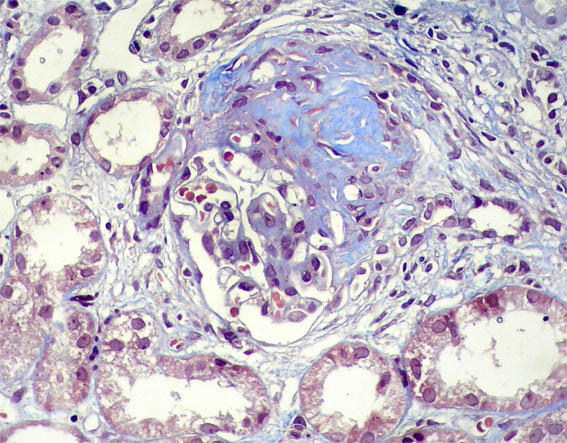

A renal biopsy was carried out. See the images:

Figure 7. Masson's trichrome stain, X200.

Figure 8. Masson's trichrome stain, X400.